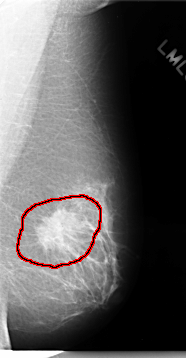

C_0075_1.LEFT_MLO

LEFT_MLO LINES 4648 PIXELS_PER_LINE 2416 BITS_PER_PIXEL 12 RESOLUTION 50 OVERLAY

FILE: C_0075_1.LEFT_MLO.OVERLAY

TOTAL_ABNORMALITIES 1

ABNORMALITY 1

LESION_TYPE MASS SHAPE IRREGULAR MARGINS SPICULATED

ASSESSMENT 5

SUBTLETY 5

PATHOLOGY MALIGNANT

TOTAL_OUTLINES 1

BOUNDARY